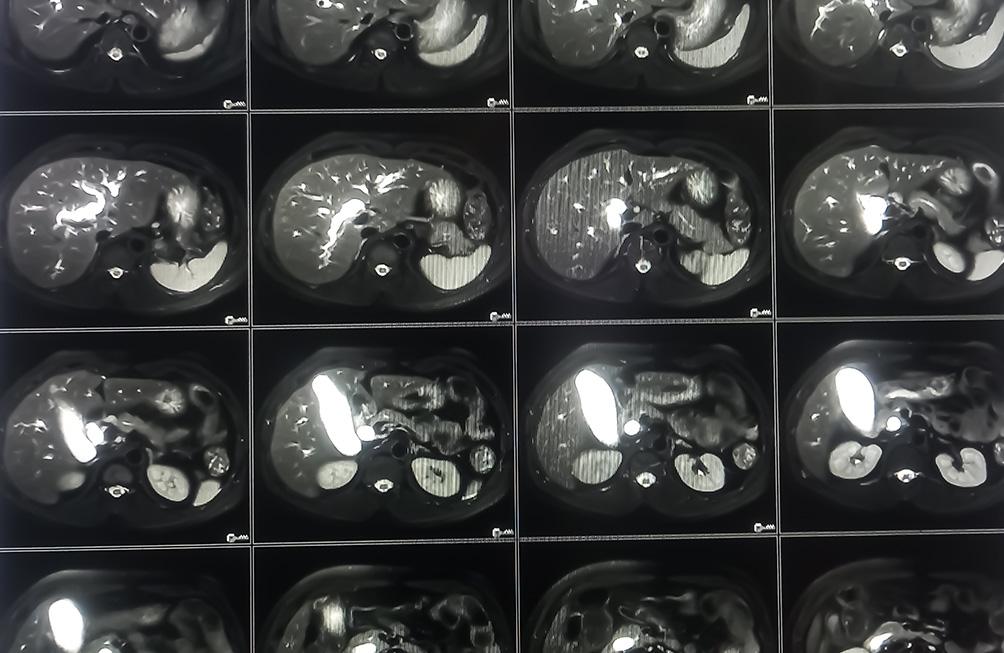

L'IRM hépatique est une méthode sûre et non invasive, réalisée afin d'évaluer la santé du foie. Elle permet :

- L'évaluation des maladies du foie telles que la cirrhose, la stéatose hépatique (foie gras) ou d’autres maladies inflammatoires.

- La recherche de lésions ou d'anomalies comme des kystes, des abcès ou des lésions tumorales.

- L'évaluation de la vascularisation hépatique notamment pour étudier la circulation sanguine dans le foie.